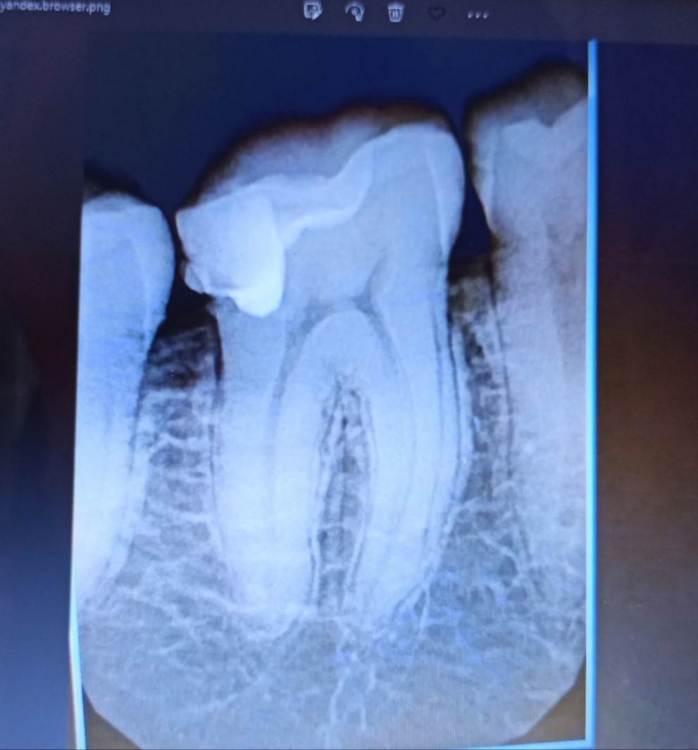

Привет, вопрос к уважаемым специалистам - Дилемма, можно ли спасти-вылечить пломбой или только коронку ставить,т.е. =умерщвлять?

Зуб нижней челюсти справа.

Снимки из КТ 2019-го года, и рентген лета 2022г.

Пломба ~2015-го.

@IvanK такие истины понятны, но вот напрягает, что уже на КТ старом вижу,что как будто пломба прямо на пульпе ...и тогда то ли я вижу совсем не то,то ли действительно так - и значит что снимая эту пломбу, точно же придется "умерщвлять"?

То есть кроме того снаружи видно что пломба большая и кариес под нее "подлез", увидел эту непонятную темноту, как будто пульпу, переходящую в пломбу и напрягся так сказать